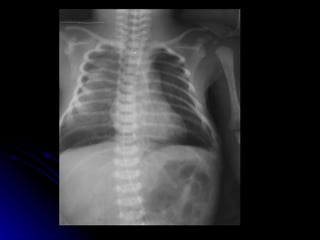

Hyaline membrane diseaseClinical:- Usually preterm Tachypnoea > 60 Indrawing/ retraction/ recession Grunting Nasal flaring Cyanosis in air Presents within a few hours of life

• 16.

• 17.

HMD - AetiologySurfactant deficiency Structurally immature lungs